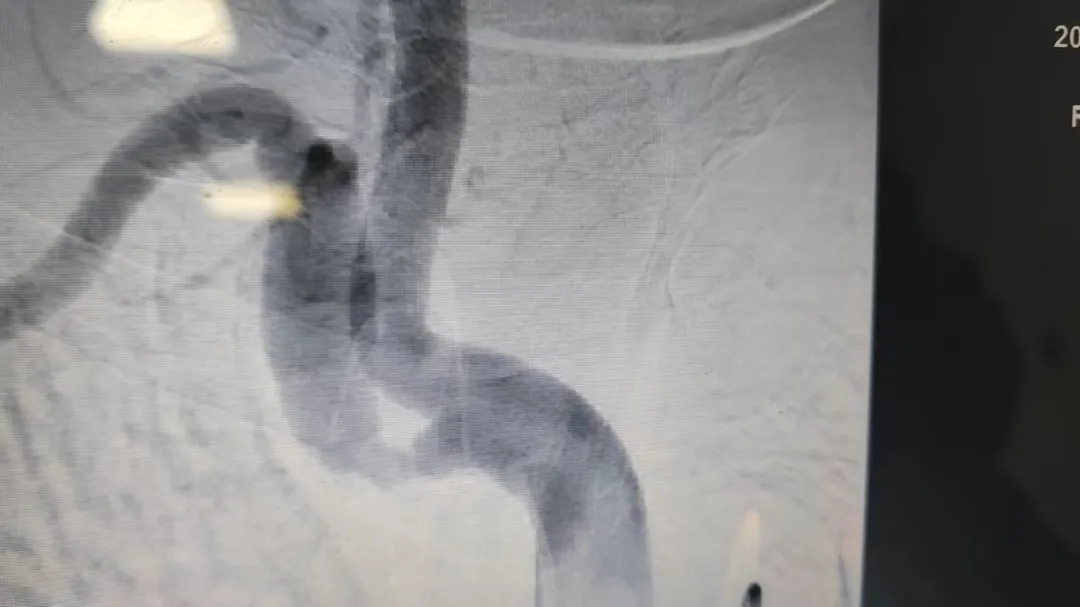

2023年检查影像

为进一步明确病情,12月23日,医生为王阿姨进行了脑血管造影检查。结果提示,其右侧锁骨下动脉狭窄程度较两年前明显加重,手术指征明确。经与家属充分沟通并取得同意后,神经内科团队随即为王阿姨施行了右侧锁骨下动脉支架植入术。手术顺利,术后造影显示血管狭窄段已被成功扩开,血流恢复通畅。